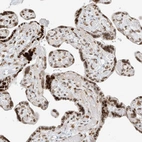

Immunohistochemical staining of human placenta shows strong nuclear positivity in trophoblastic cells.